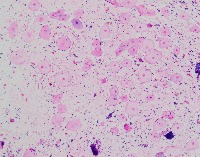

Medical Image Analysis: geckler3 could be used by healthcare professionals, researchers, and medical students to quickly and accurately identify White Blood Cells (WBC) and Erythrocyte-Hemoglobin Concentration (EHC) in clinical images, improving diagnosis and understanding of various blood-related conditions and diseases.

Blood Disorder Diagnosis Support: Implement geckler3 in diagnostic tools to assist doctors in identifying blood disorders, such as anemia or leukemia, by accurately analyzing WBC and EHC levels in blood images, helping with faster and precise diagnosis and treatment.

Biomedical Research: Utilize geckler3 in research laboratories for various biomedical and biotechnological studies to analyze large datasets of blood images, streamlining the process of data collection and analysis by automatically detecting WBC and EHC patterns.

Training and Educational Tool: Integrate geckler3 into educational platforms or applications to help medical and laboratory professionals, as well as medical students, learn and practice the identification of WBC and EHC in blood images, enhancing their skills and knowledge.

Remote Diagnosis Assistance: Employ geckler3 in telemedicine applications, allowing healthcare professionals to remotely access and analyze blood images for the presence of WBC and EHC, aiding in the diagnosis and management of blood-related conditions in areas with limited medical facilities.